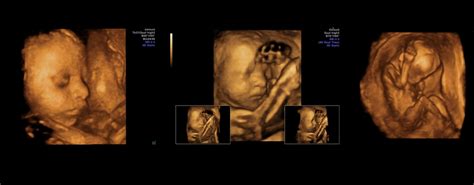

Morfologia fetală, cunoscută și sub denumirea de ecografie de morfologie fetală, este o procedură imagistică non-invazivă utilizată pentru a evalua anatomia fătului și a detecta eventualele anomalii congenitale. Această examinare se realizează, de obicei, între săptămânile 18 și 22 de sarcină, când majoritatea organelor și sistemelor corpului fetal sunt suficient de dezvoltate pentru a fi vizualizate clar.

Prin intermediul ecografului, medicul specialist poate examina în detaliu structura corpului bebelușului, inclusiv inima, creierul, rinichii, membrele și coloana vertebrală. De asemenea, se verifică poziția placentei, cantitatea de lichid amniotic și lungimea colului uterin.

În urma examinării, medicul va interpreta imaginile ecografice și va discuta cu părinții despre starea de sănătate a fătului. Raportul ecografic va conține informații detaliate despre măsurătorile efectuate, dezvoltarea organelor și eventualele constatări. În cazul în care se identifică o anomalie, medicul va recomanda investigații suplimentare și va oferi consiliere părinților.